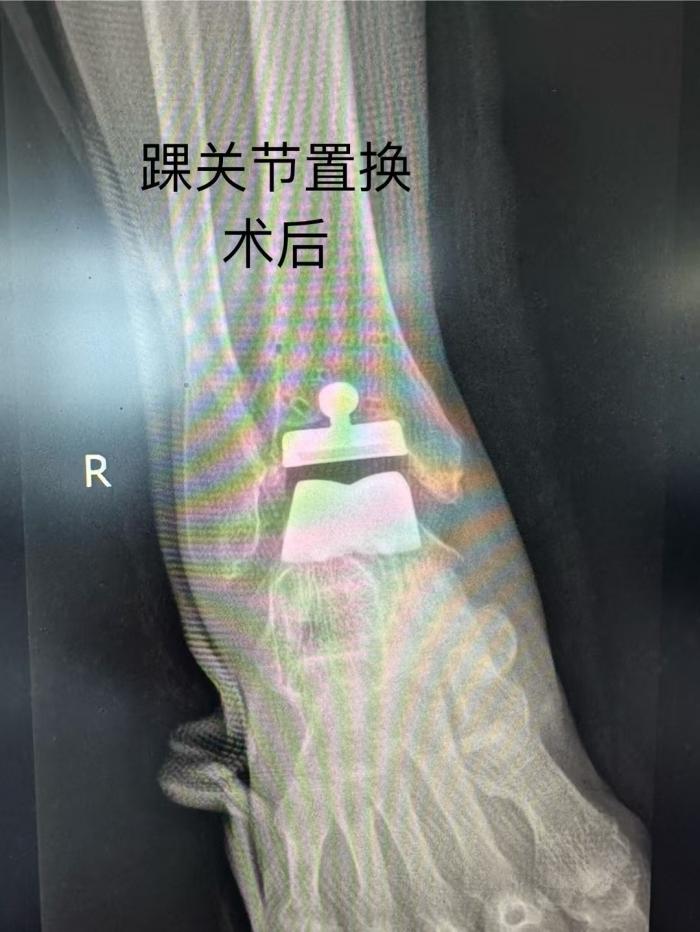

![]()

手术中,唐新文团队依托患者 CT 数据完成踝关节三维重建,通过3D打印技术 1:1 定制截骨导板,实现与骨性标志100% 贴合,将截骨误差严格控制在0.5mm以内(传统徒手操作误差达2-3mm)。借助导板精准引导,仅通过前侧7cm微创切口,便完成假体植入,手术耗时120分钟(较传统术式缩短60分钟),出血量控制在 100ml 以内,全程无需输血。术中通过导板预设的解剖参数优化,选择的第三代解剖型假体与骨骼接触面积增加 35%,配合仿生曲面设计及多孔涂层促进骨长入,显著降低术后松动风险。

术后,欧阳阿姨恢复情况良好。在麻醉苏醒后,她就在护士的指导下开始进行跖屈、背伸及直腿抬高训练。72 小时后,疼痛评分降至3分(VAS)。术后第5天,她已经能够使用助行器下地行走。欧阳阿姨开心地说:“现在脚踝轻松多了,也没那么痛了,就等着和老伴一起出院了。” 与此同时,同期接受人工股骨头置换术的老伴也恢复良好,预计本周可出院。